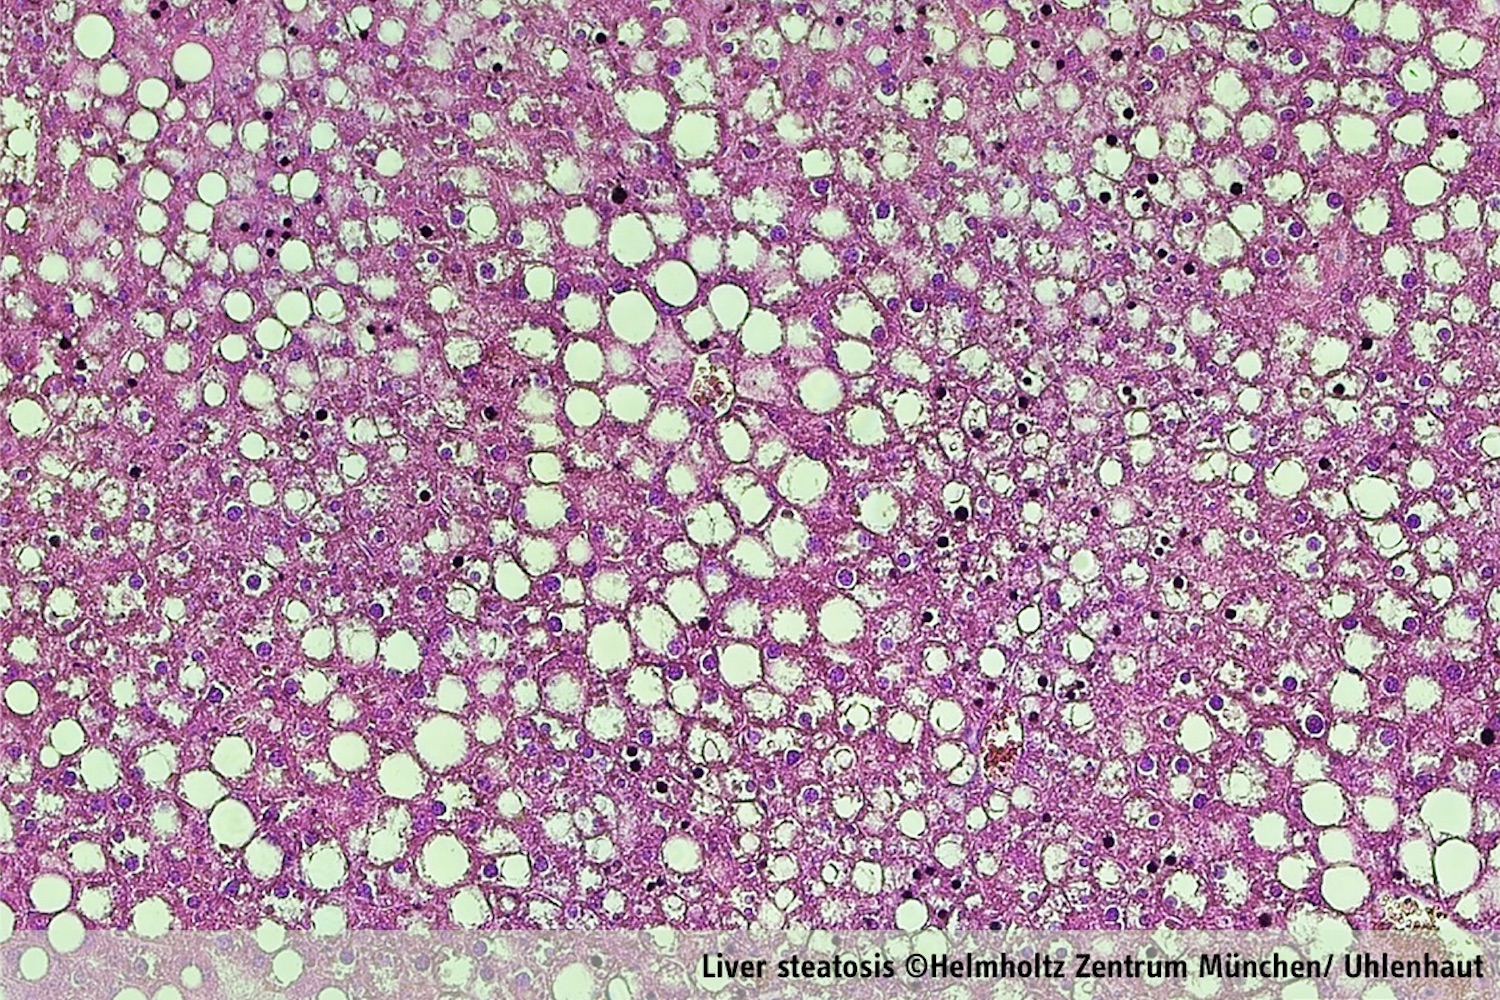

Each cell in the human body is driven by an internal clock which follows the circadian rhythm of 24 hours. It is synchronized with the natural cycle of day and night mainly by sunlight, but also through social habits. In a healthy system, glucocorticoid stress hormones, are produced every morning by the adrenal gland. The secretion of glucocorticoidpeaks before awakening, prompting the body to use fatty acids and sugar as sources of energy, and enabling us to start our daily activities. When the circadian rhythm is disrupted (e.g. through shift work or jetlag) and/or when the glucocorticoid level alters (e.g. through Cushing syndrome or long-term clinical application), profound metabolic dysregulation can be caused – like obesity, type 2 diabetes, and fatty liver disease. The researcher’s goal therefore was to understand the relevance of these daily peaks of stress hormone secretion, the impact of these hormones on our “internal clock” and their role for daily cycles of metabolism.

Glucocorticoids are a group of natural and synthetic steroid hormones such as cortisol. They have potent anti-inflammatory and immunosuppressive properties which can control the activity of the immune system. This is why they are widely exploited in medicine. The major drawback is that glucocorticoids also cause severe side effects by virtue of their ability to modulate sugar and fat metabolism: Patients may develop obesity, hypertriglyceridemia, fatty liver, hypertension or type 2 diabetes.